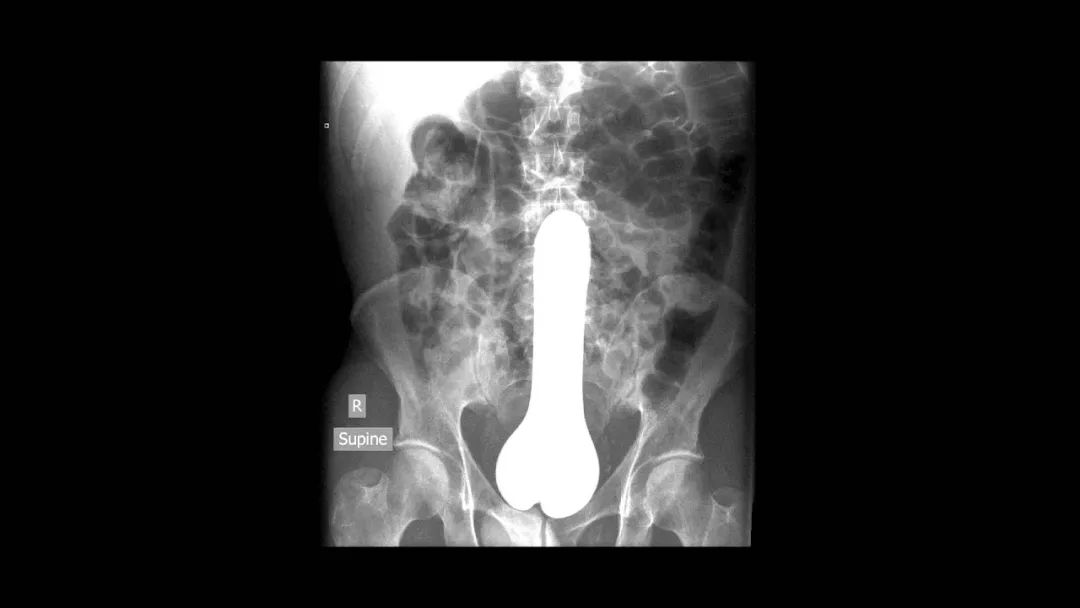

又到了大家最喜歡的看圖猜異物環節

請將答案按順序寫在評論區